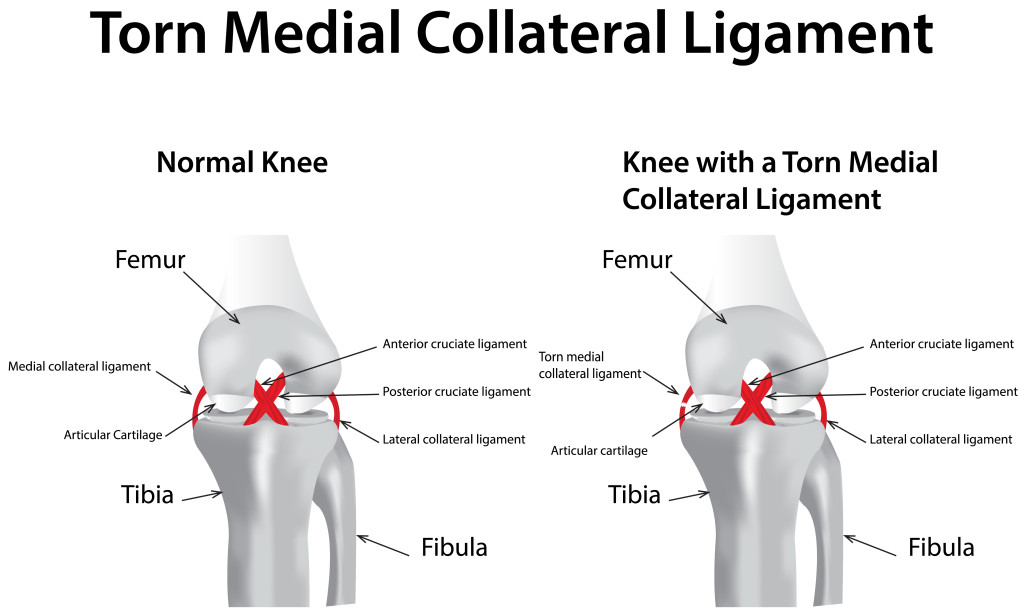

There are two primary types of mcl surgery: While most mcl injuries can resolve without surgery, there are instances where surgery is the best treatment option. You’ll need to raise your sore knee when you put ice on it, keep weight off the joint, and protect and compress the injury with a knee brace or elastic bandage.

Treatment options for an mcl sprain. The surgery will either repair or reconstruct the mcl. A total rupture of the mcl usually doesn’t require surgery.